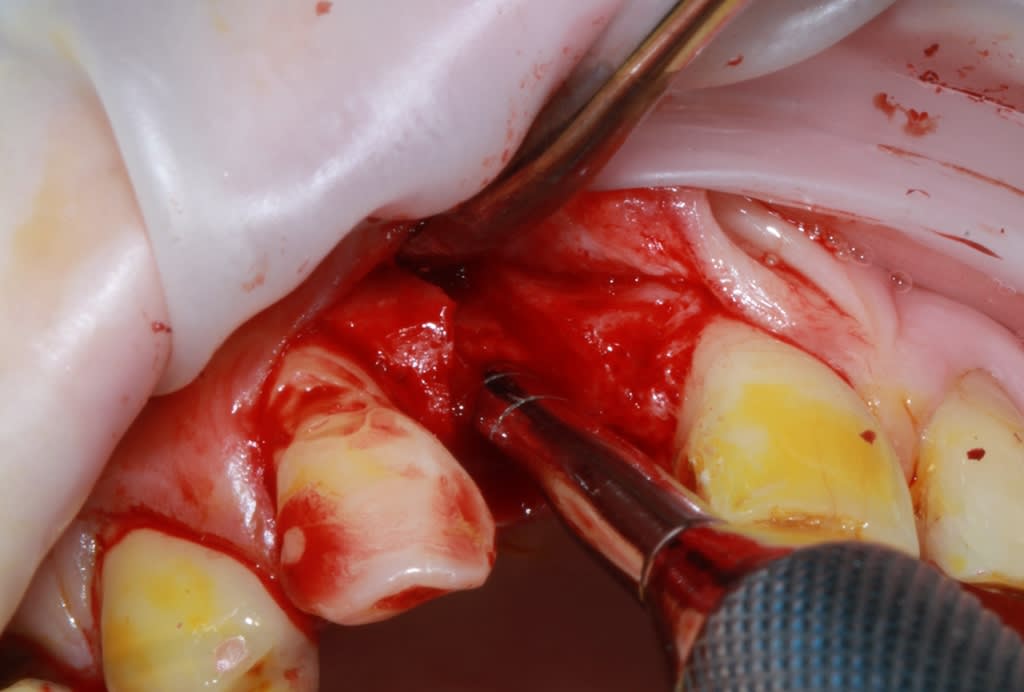

Thomas, tu as un plan pour guider dans un cas comme ça?

ou comment remplacer 12 avec soucis vestibulaire, par un implant, sans greffe, sans ROG, juste avec les mimines....?

vue de l’intérieur..

Pas de comblement pour epaissir le rempart vestibulaire ? tu ne crains pas une résorption dans le temps de ce spongieux amené en vestibulaire ?